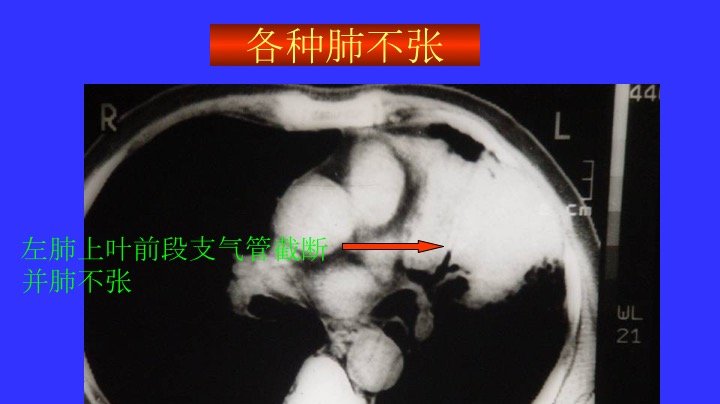

胸部CT阅读与诊断(三)各种肺不张